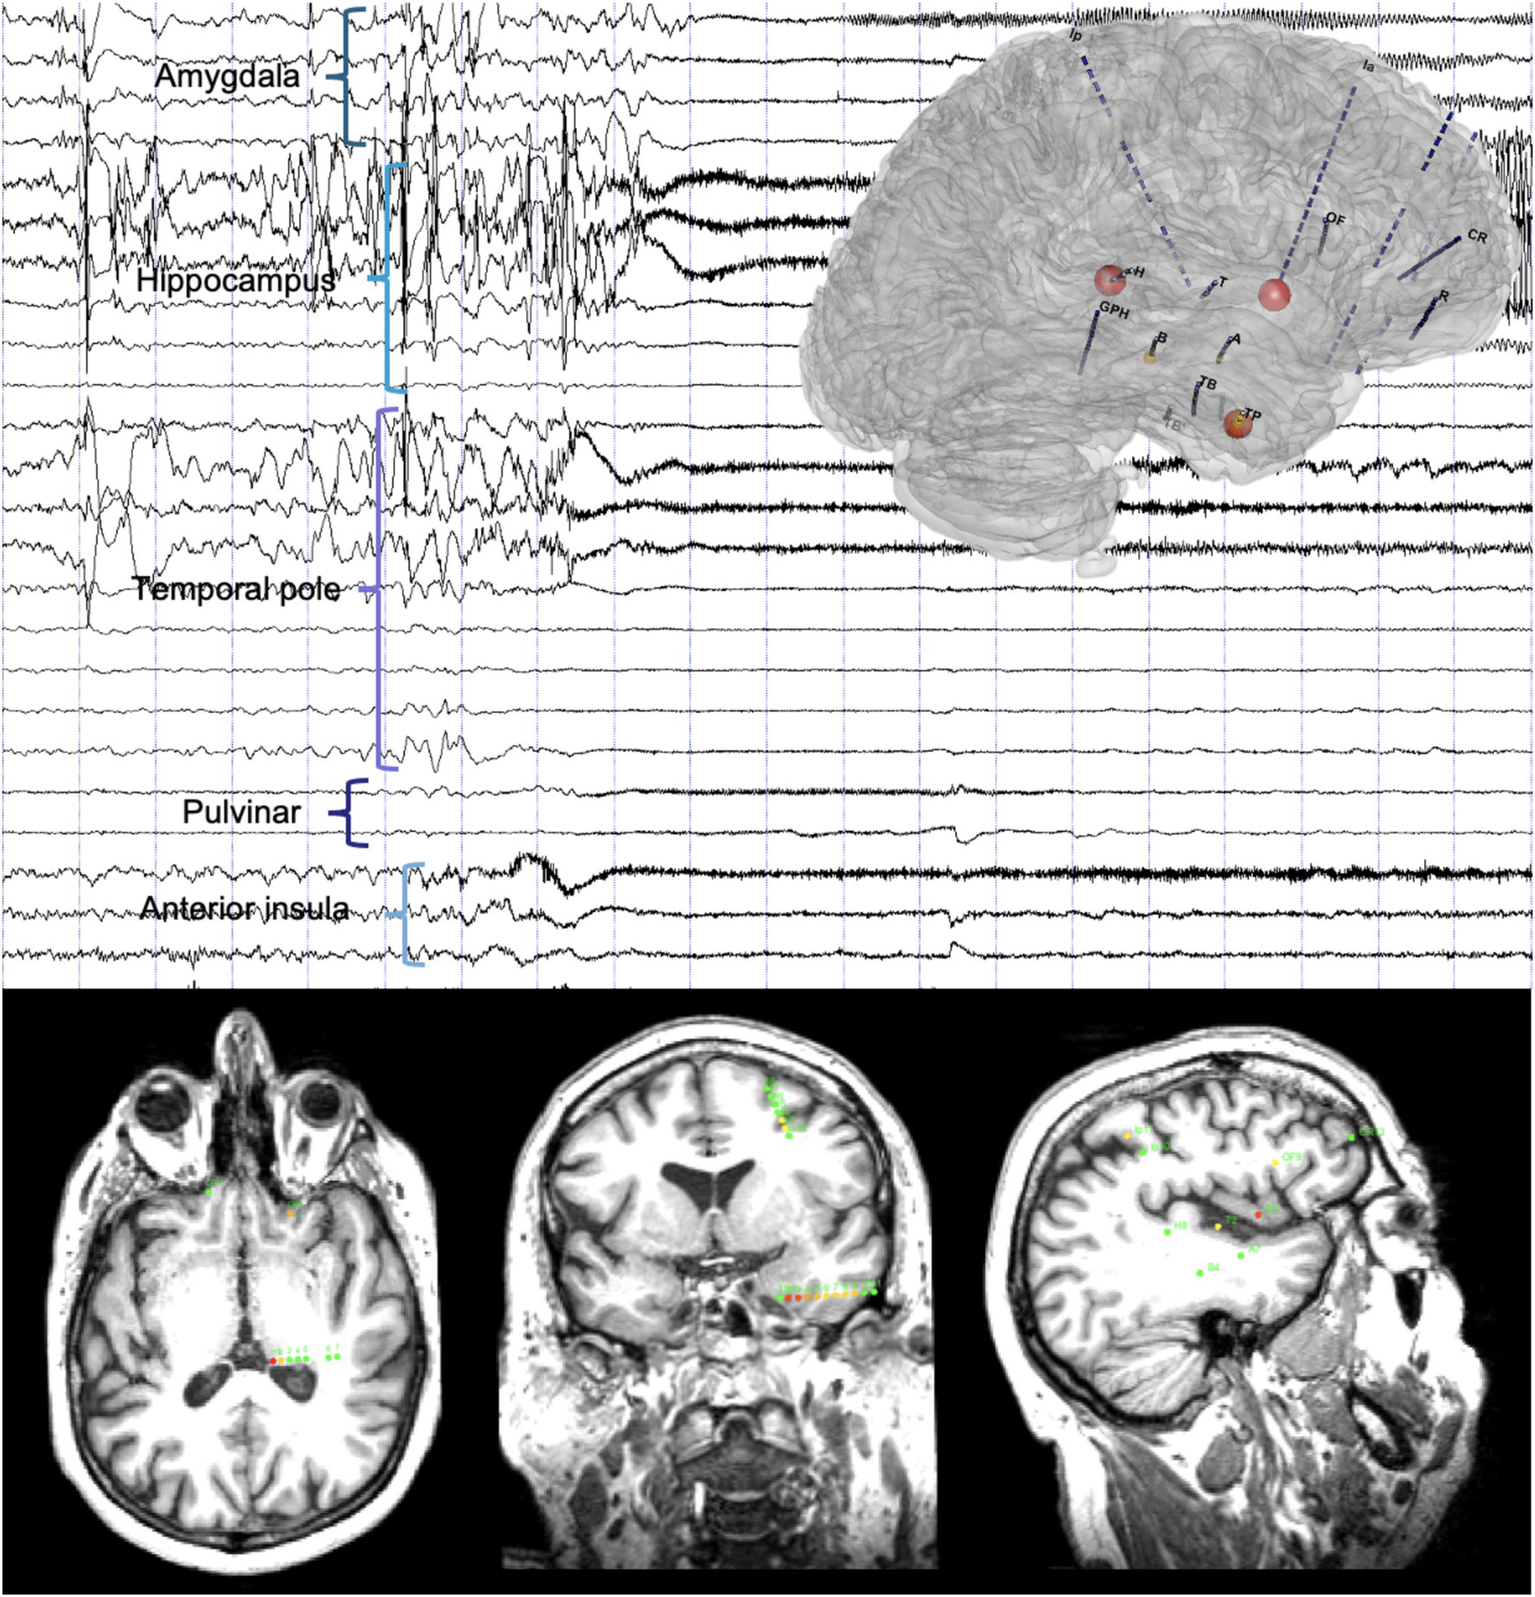

Ictal SEEG recordings with available sampling of subcortical brain areas demonstrated thalamic implication during the first 15 s of the seizure in 86% of patients based on visual analysis (8, 20) (Figure 2).

Figure 2

Timing of the thalamic implication in a temporal lobe seizure. Top: A 20-s SEEG recording dataset including a temporal lobe seizure and three-dimensional representation of the epileptogenicity index (EI). Seizure-onset is characterized by a DC-shift with low-voltage fast activity involving the anterior insula and the temporal pole, rapidly involving the pulvinar, and later amygdala and hippocampus. Bottom: Axial (left), coronal (middle) and sagittal (right) slices of T1-weighted brain MRI with a representation of the normalized EI values on the respective intracranial contacts (for details on the EI, see Bartolomei et al. (31), involved contacts represented according to a color scale from yellow to red, green contacts non involved in the discharge): Ia1-2 (anterior insula, right), EI = 1; H1-2 (pulvinar, left), EI = 0.97; TP2-3, TP3-4 and TP4-5 (temporal pole, middle), EI = 0.89 to 0.44.